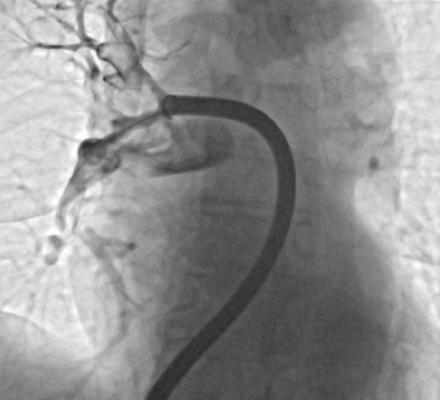

V Splošni bolnišnici Murska Sobota so naredili pomemben korak v razvoju sodobne medicine, saj so uspešno izvedli prvo mehansko odstranitev krvnega strdka iz pljučne arterije.

Poseg je opravil interventni kardiolog Danijel Crnčić ob podpori zdravnikov internistov kardiologov, Urške Bencak Ferko in Dušana Kovača ter celotne ekipe interventne kardiologije, kar predstavlja pomemben mejnik za zdravljenje ene najnevarnejših žilnih bolezni.

V zadnjih letih pa se vse bolj uveljavlja sodobnejši pristop, to je mehanska odstranitev strdka s katetrom. Gre za minimalno invaziven poseg, pri katerem zdravnik skozi veno, običajno v dimljah, uvede kateter in ga pod nadzorom vodi do mesta zapore. Nato s posebnim sistemom ustvari podtlak in strdek fizično odstrani iz žile.

Foto: Splošna bolnišnica Murska Sobota